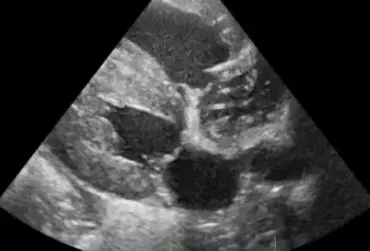

Echo serca z widoczną obecnością dużej liczby nicieni w prawym przedsionku serca (1)

16 kwietnia 2019

Wojciech Atamaniuk

Czytaj więcej